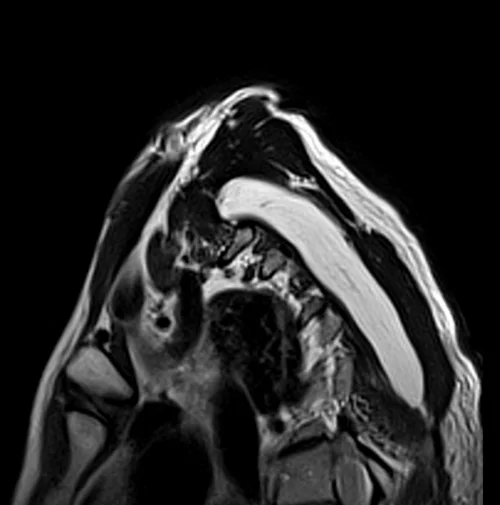

MRI brachial plexus sagittal oblique T2 images